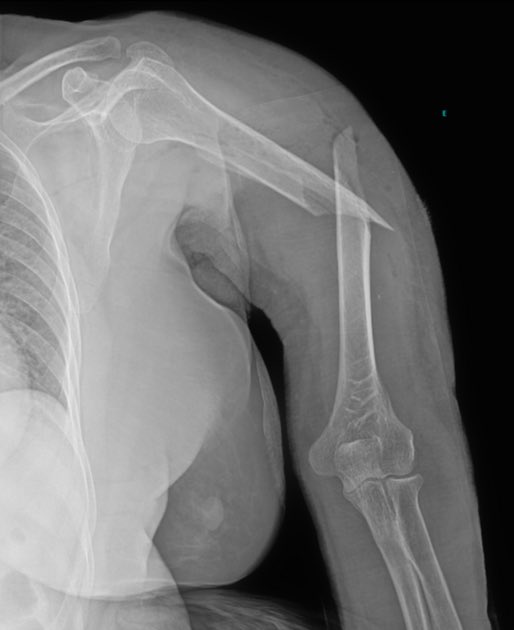

Mid fracture of the Humerus, Which principal vessel is lesioned?

Sage_medics's tweet image. Mid fracture of the Humerus, Which principal vessel is lesioned?